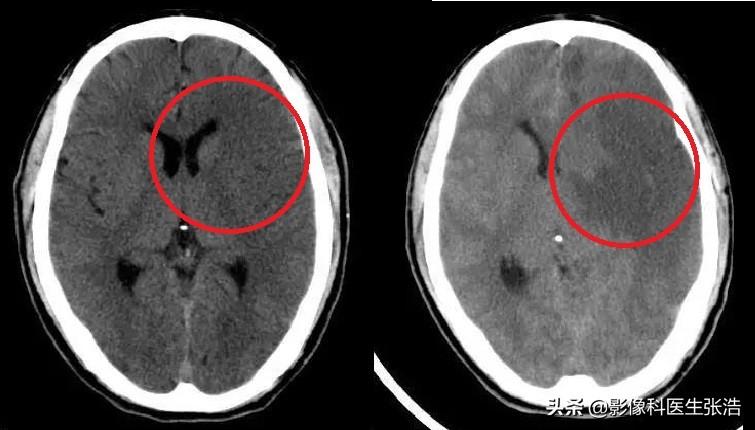

腦梗的診斷

腦梗的診斷主要依據(jù)患者的病史、體格檢查和影像學檢查,醫(yī)生會根據(jù)患者的癥狀、體征以及可能的病因進行初步判斷,并結合頭顱CT、MRI等影像學檢查來確診。